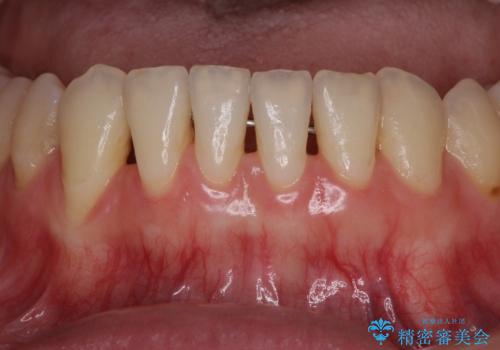

下顎前歯の歯肉退縮 歯肉移植による根面被覆

担当医 藤巻太一朗